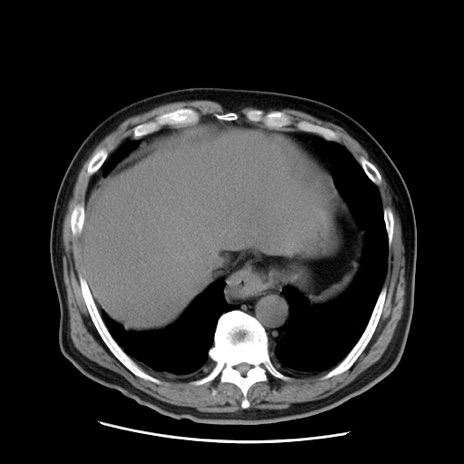

症例20(横断像)

【症例】 60歳代男性

【主訴】 腹部膨満、嘔吐

【現病歴】5日前頃より倦怠感を認め食事量減少し4日前の朝嘔吐、食事摂取困難となった。 3日前近医受診し点滴施行され整腸剤などを処方された。 当日他院を受診し、腹部膨満著明、炎症反応の上昇(CRP10.8、WBC11200)あり、紹介受診となる。

【身体所見】 意識JCS1 受け答えがはっきりしないBP 111/57mHg、 P 67bpm、、BT35.2°C、SpO2 97%(RA)、 腹部:膨隆、打診で鼓音あり、全体的に圧痛有り、腸蠕動音(-)、反跳痛ははっきりせず。

【データ】WBC 11400、CRP 14.20